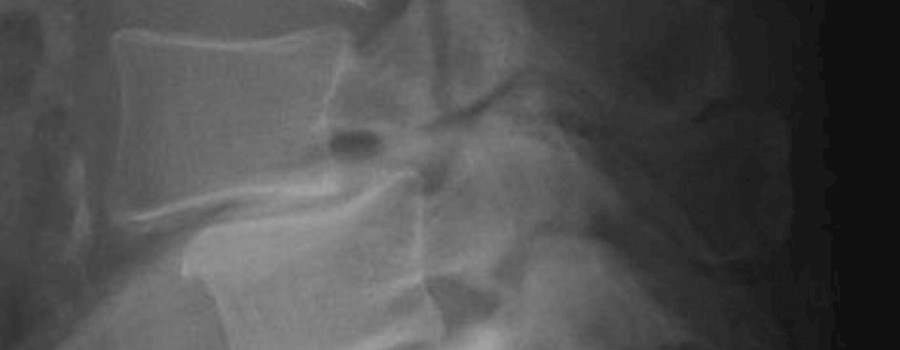

Bis zu sechs Prozent der Bevölkerung weisen nach Abschluss der Wachstumsphase einen Spalt im Gelenkfortsatz eines Wirbels auf. Diese Spondylolyse bleibt oft asymptomatisch, kann aber auch zum Wirbelgleiten führen.